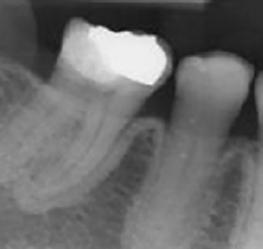

Radiologiquement, le tableau clinique de l'ostéonécrose de la mâchoire se manifeste très tôt par une augmentation de la sclérose de l'os. Celle-ci apparaît souvent d'abord au niveau de la lamina dura de l'os alvéolaire, bien avant que la nécrose de la mâchoire ne se manifeste cliniquement (stade 0 – illustration 1). Dans les cas

Lamina dura sclérosée comme signe précoce d'une exposition accrue aux médicaments antirésorptifs (stade 0)

(photo avec l'aimable autorisation du Dr H. Thuau)

Abbildung 1: Sklerosierte Lamina dura als Frühzeichen einer verstärkten Exposition durch antiresorptive Medikamente (Stadium 0) (Bild mit freundlicher Genehmigung Dr. H. Thuau)